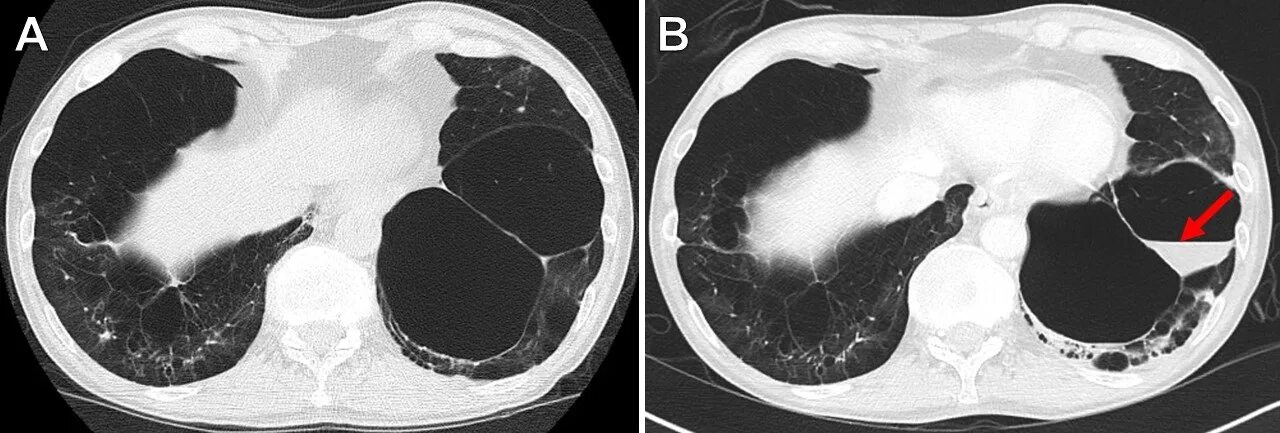

Патологическое содержимое что это